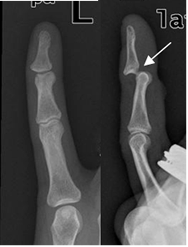

Fig 57. Luxación de los dedos.

A: Rx AP. No se aprecian anormalidades.

B: Rx lateral. Luxación posterior de la articulación interfalángica distal.

Fig 58. Amputación del dedo.

Rx AP. Amputación sobre la mitad de la falange media del 3º dedo, con desplazamiento medial e inferior.